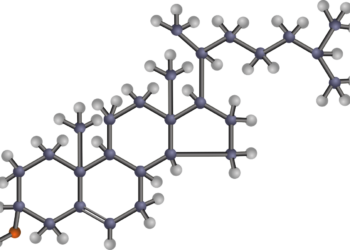

쿠바산 폴리코사놀의 효능 ‘HDL’기능 개선 효과, 『대한기능의학회』학술지 게재

심혈관건강 지키려면 LDL은 낮추고 HDL의 품질과 양은 높여야 전세계 사망원인 1위인 심혈관질환의 주요 원인 중 하나는 콜레스테롤이 축적되면서 염증이 발생하고...

쿠바산 폴리코사놀 ‘대사증후군’ 환자의 콜레스테롤 조절 효과

폴리코사놀 LDL 13.8% 낮추고, HDL 8.7% 높여 쿠바산 폴리코사놀이 대사증후군 환자들에게 효과가 있다는 연구결과가 내분비학회지(J Endocrinol Metab) 최신호에 게재되었다. 대사증후군이란...